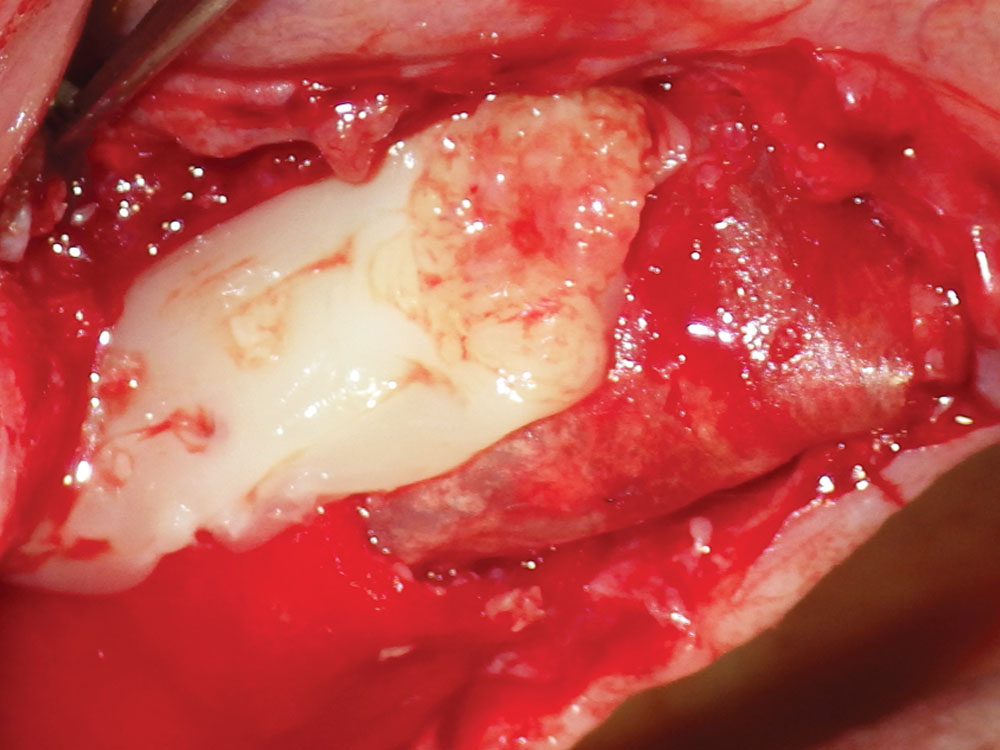

Bone Growth Factors

Bone growth factors may be used in combination with barrier membranes to enhance the formation and mineralization of bone, especially in larger cases. In addition, bone growth factors may induce undifferentiated mesenchymal cells to differentiate into bone cells that trigger a cascade of intracellular reactions for the release of additional bone growth and cell-enhancing factors. The two most common bone growth factor techniques utilize blood concentrates (platelet-rich fibrin) and recombinant human bone morphogenetic protein-2. Multiple clinical studies have shown increased soft-tissue healing, enhanced healing of grafted bone, promotion of angiogenesis, and faster wound healing with the use of bone growth factors (Fig. 15).8

Platelet-rich fibrin growth over barrier membrane

Figure 15: Platelet-rich fibrin (PRF) growth factor placed over the barrier membrane. PRF can also be mixed with the bone graft material for increased bone healing results. See more details about PRF procedures in Dr. Resnik’s article, “Enhancing Bone Regeneration with the Use of Platelet Concentrates” (Chairside® Vol. 15, Issue 1).